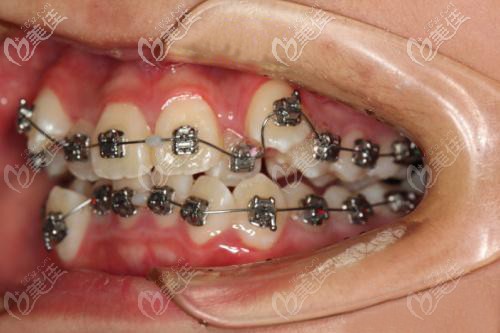

术后照片:

方案二:不拔牙,采用诊断性矫治设计方案,使用金属自锁托槽矫治器。

2、担心戴传统的钢牙套太过于磨嘴、不适,戴可摘戴的隐形牙套又嫌麻烦.....所以,就选择了进口的3M金属自锁托槽。

3、自锁托槽上面少了结扎丝的捆绑,降低摩擦力,戴上相对会舒适一些,还能延长复诊时间。

还有就是,我了解到未成年人的牙槽骨还在发育期,所以矫正的时间也要比成年人快一些,这位17岁的小妹妹就只用了14个月,成人的话少说也要2年左右。